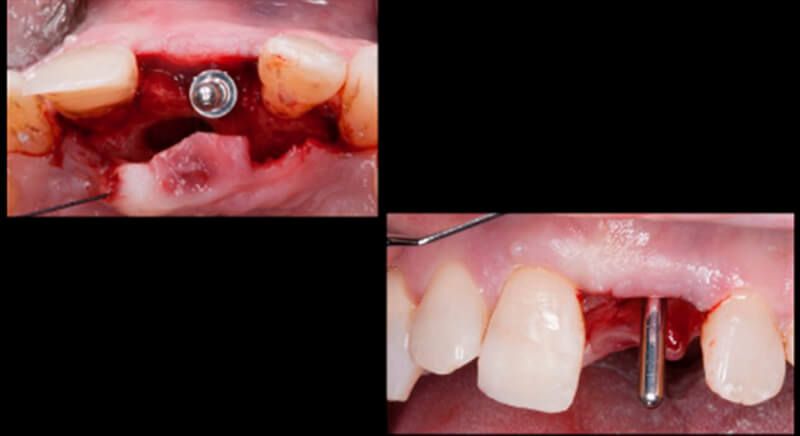

The guided surgery was performed by lifting a full thickness mucoperiosteal flap. A Biomimetic Ocean CC implant, diameter 3.5mm and length 10mm, was inserted using the surgical guide in the ideal three-dimensional position and the defects were regenerated with xenograft and reabsorbable membrane, the nasopalatine duct on the palatine side and the area of dehiscence on the vestibular.

During the same surgical intervention, a short 3mm Avinent healing abutment was positioned and fully covered by the flap. Primary closure was completed and we waited 6 months for the bone graft to mature.